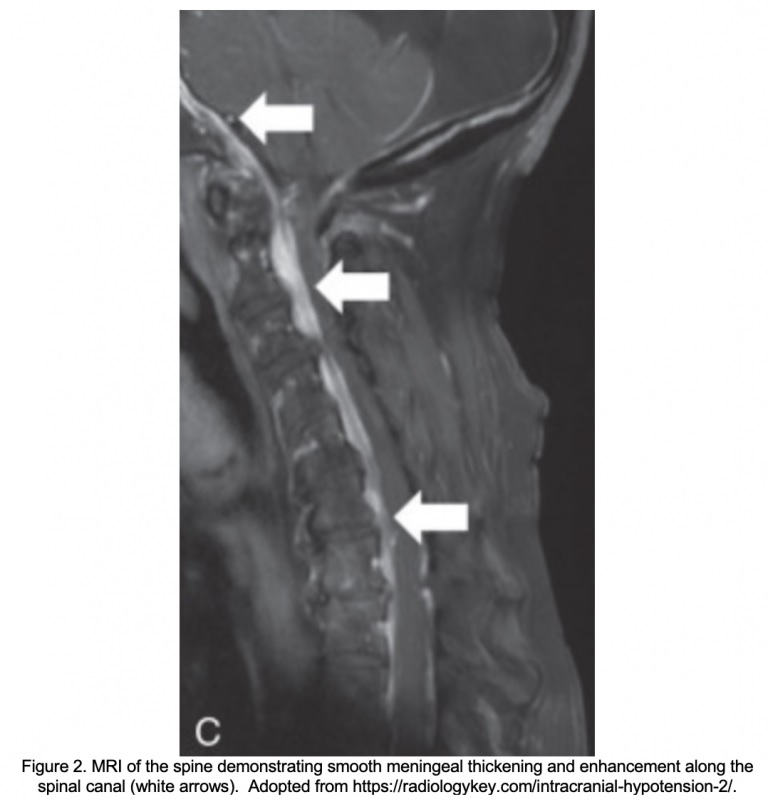

IRM de la colonne vertébrale . L’obtention d’une IRM de la colonne vertébrale peut être utile pour identifier la source de la fuite du LCR. Les résultats d’une IRM de la colonne vertébrale comprennent une fuite de liquide péridural, la présence de diverticules méningés, une accumulation de liquide dans la cavité extraméningée et un rétrécissement du sac dural avec distension concomitante du plexus veineux épidural.

Myélographie . La myélographie de contraste iodée de l’ensemble de la colonne vertébrale (ou au gadolinium suivie d’une IRM) s’est révélée être l’étude de choix pour définir avec précision la localisation et l’étendue d’une fuite de LCR. Bien que de multiples fuites soient fréquemment constatées le long de la colonne vertébrale, la plupart des fuites de LCR se trouvent à la jonction cervico-thoracique ou le long de la colonne thoracique.

Le patient a subi une tomodensitométrie cérébrale et une CTA qui n’ont montré aucune anomalie intracrânienne aiguë. Une IRM du cerveau a ensuite été obtenue, révélant un rehaussement pachyméningé diffus, un épaississement et un engorgement du sinus veineux dural. Le patient a été admis à l’unité d’observation pour des examens plus approfondis, notamment une IRM T/L de la colonne vertébrale, qui a montré une importante accumulation de liquide péridural, probablement due à une lésion de la gaine de la racine nerveuse T5-T6. Elle a consulté un anesthésiologiste, s’est fait poser un patch sanguin péridural et a pu rentrer chez elle avec la résolution de ses symptômes.